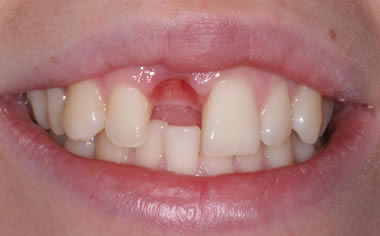

Before & After Gallery

More front teeth replaced by dental implants

Case Three (4 images)